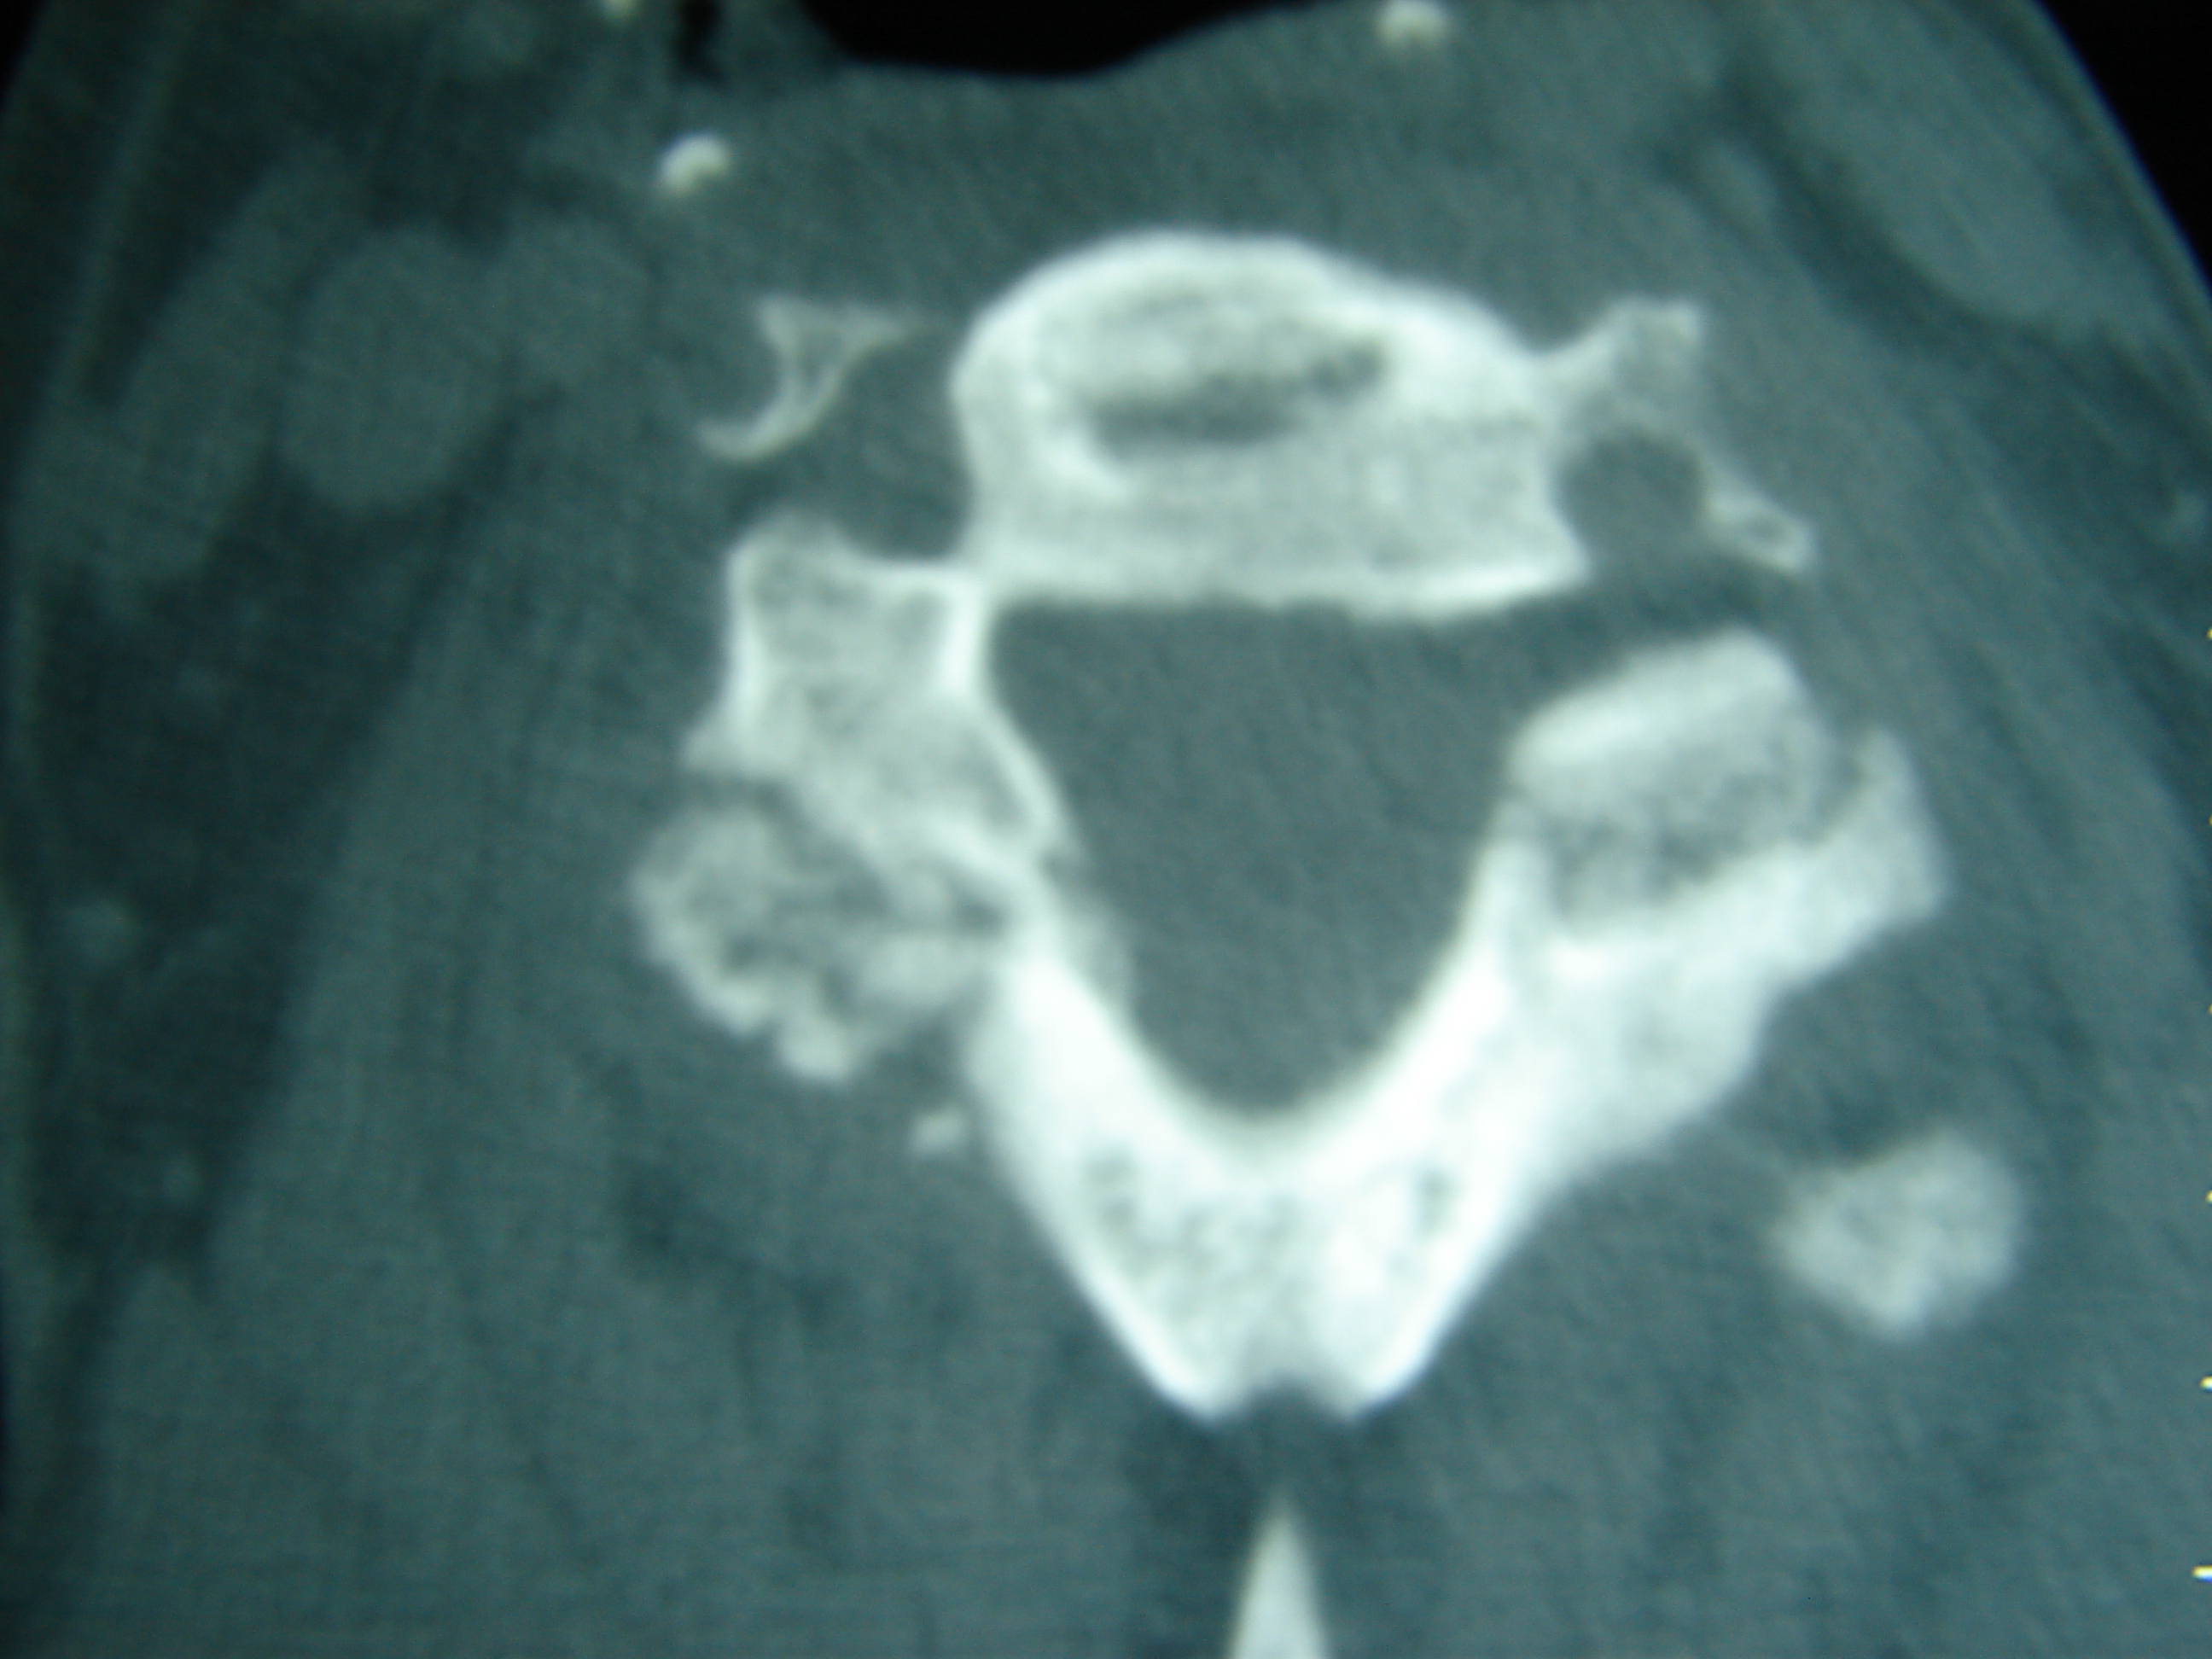

Εικόνα 4 – Αξονική τομογραφία της Α.Μ.Σ.Σ.

α,β,γ Μετωπιαία λήψη

δ,ε,ζ,η,θ,ι Πλάγια λήψη

κ,λ Εγκάρσια λήψη

Είναι εμφανής ο διαχωρισμός των σπονδυλικών σωμάτων προσθείως μεν στο επίπεδο του μεσοσπονδυλίου δίκου και οπισθίως διαμέσου των σπονδυλικών διαρθρώσεων.